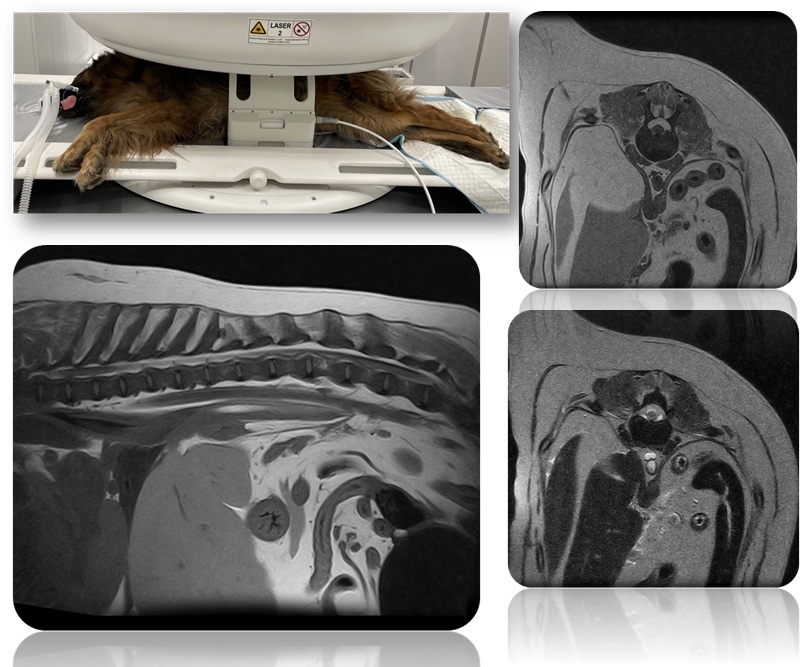

Клінічний приклад МРТ головного мозку собаки у різних проекціях, що демонструє високу деталізацію анатомічних структур

Чітка візуалізація попереково-крижового відділу хребта великої собаки вагою 58 кг на ветеринарному МРТ Magnifico Vet